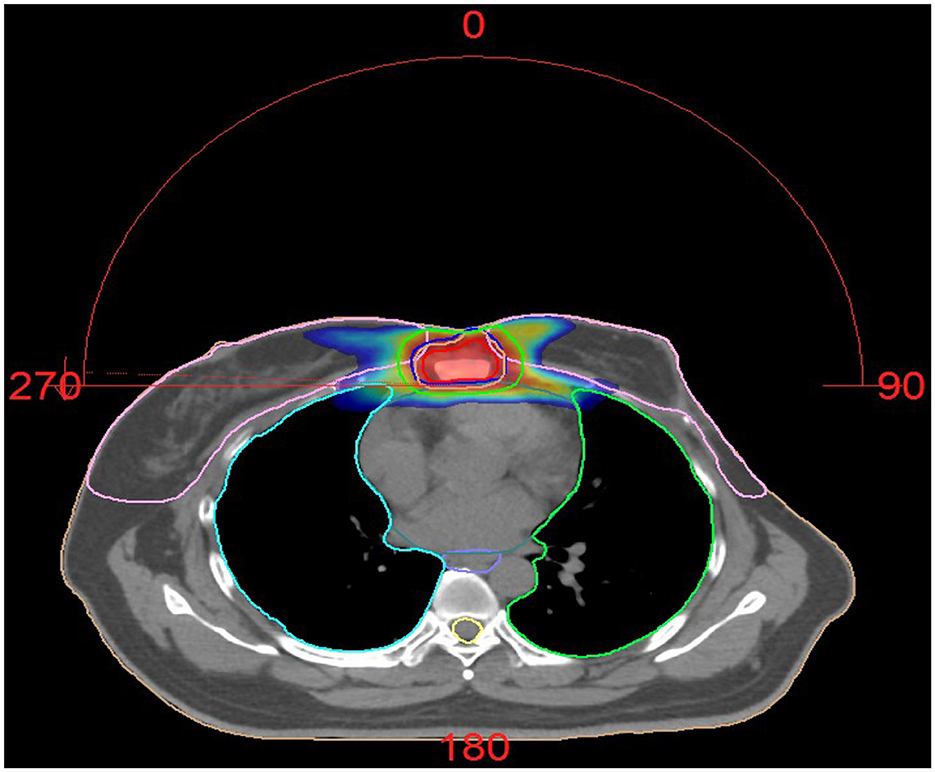

Five months later, she resumed menstruation, prompting the addition of goserelin (ovarian suppression therapy). However, due to intermittent goserelin non-adherence, menses recurred before therapy was reinstated. Three years later, she was hospitalized for cough and fever. CT showed stable subpleural lung nodules and right hilar lymphadenopathy, chronic inflammatory changes in bilateral upper/lower lobes, and unchanged sternal metastases. Influenza B screening was weakly positive (+/-). Antiviral therapy resolved her fever, but she continued to experience intermittent cough with white mucoid sputum. Six months later, repeat CT revealed worsening right lung inflammation and pleural thickening. Bronchoscopy identified a lesion in the right intermediate bronchus; biopsy and cytology confirmed metastatic breast cancer (supported by histology, IHC, and clinical history). She continued toremifene + goserelin. One year later, her regimen was adjusted to letrozole + goserelin. Six months thereafter, CT showed slight progression of lung nodules (right upper lobe, left lower lobe). She was switched to goserelin + anastrozole + palbociclib, though anastrozole was later replaced with exemestane due to gastric intolerance. For persistent sternal pain, she received palliative radiotherapy (60 Gy/25 fractions) (Figure 2).

Figure 2. Dose distribution of Patient 2 treated with radiotherapy. Palliative radiotherapy was administered for the sternal metastasis using VMAT (Volumetric Modulated Arc Therapy) technique of IMRT (Intensity-Modulated Radiation Therapy). The plan was highly optimized to ensure adequate dose coverage to the target volumes while strictly limiting the radiation dose to surrounding normal organs (such as the heart, spinal cord, and lung tissue), keeping them within safe tolerance limits. The procedure was well tolerated. The prescribed dose was: GTV 60 Gy in 25 fractions, CTV 50 Gy in 25 fractions.